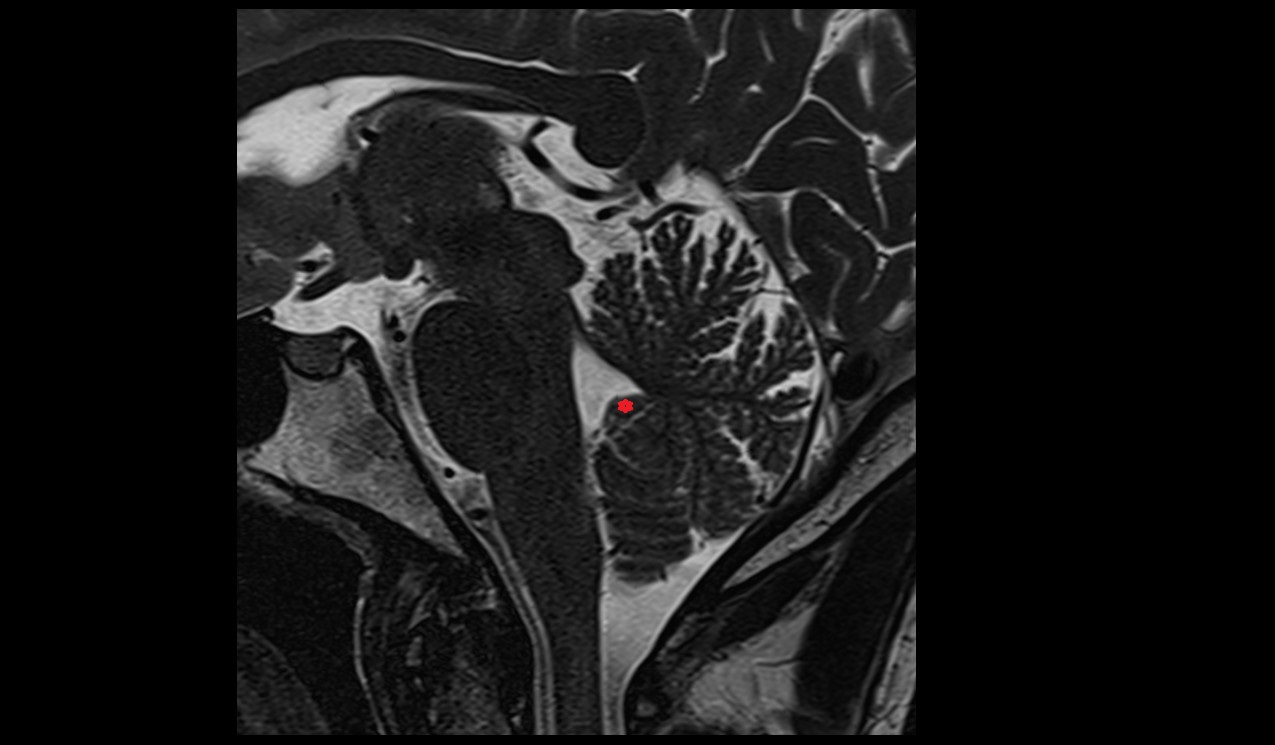

- Cerebellum

- Tonsil of cerebellum

- Cerebellar tonsil (H IX)

- Fourth ventricle

- Cisterna magna